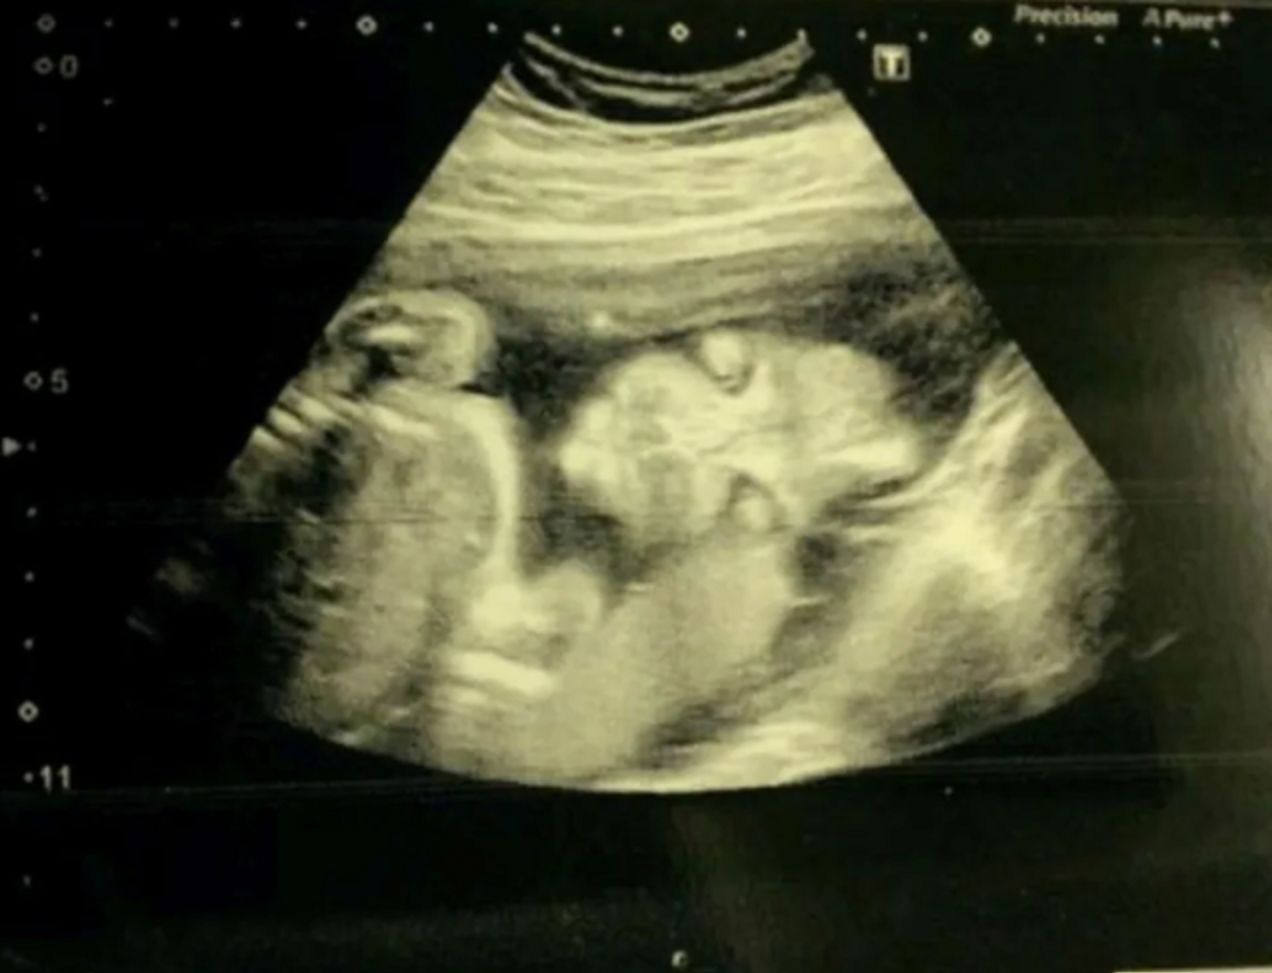

Okazało się jednak, że dziewczyna cierpi na inną chorobę, gdy kilka miesięcy później trafiła do szpitala. Rodzice byli zaniepokojeni nietypowym zachowaniem ich pociechy, która nieustannie "pocierała czoło i bawiła się włosami". Po wykonaniu badań lekarze znaleźli w jej głowie guzy.

Rose po raz kolejny trafiła do szpitala. Spędziła tam wiele nocy i przeszła aż trzy operacje mózgu. Po tygodniu lekarze wrócili do rodziców z tragiczną diagnozą. Okazało się, że Rose ma teratoidalnego guza rabdoidalnego, czyli raka rzadkiej postaci atakującego ośrodkowy układ nerwowy. To oznaczało dla niej wyrok.

U dziewczynki znaleziono dużego guza w kręgosłupie, który atakował także układ trawienny, przez co miała problemy z jelitami. Rodzice usłyszeli, że małej Rose pozostało jedynie kilka tygodni życia. Zmarła w dziecięcym hospicjum dwa dni po swoim pierwszych urodzinach.